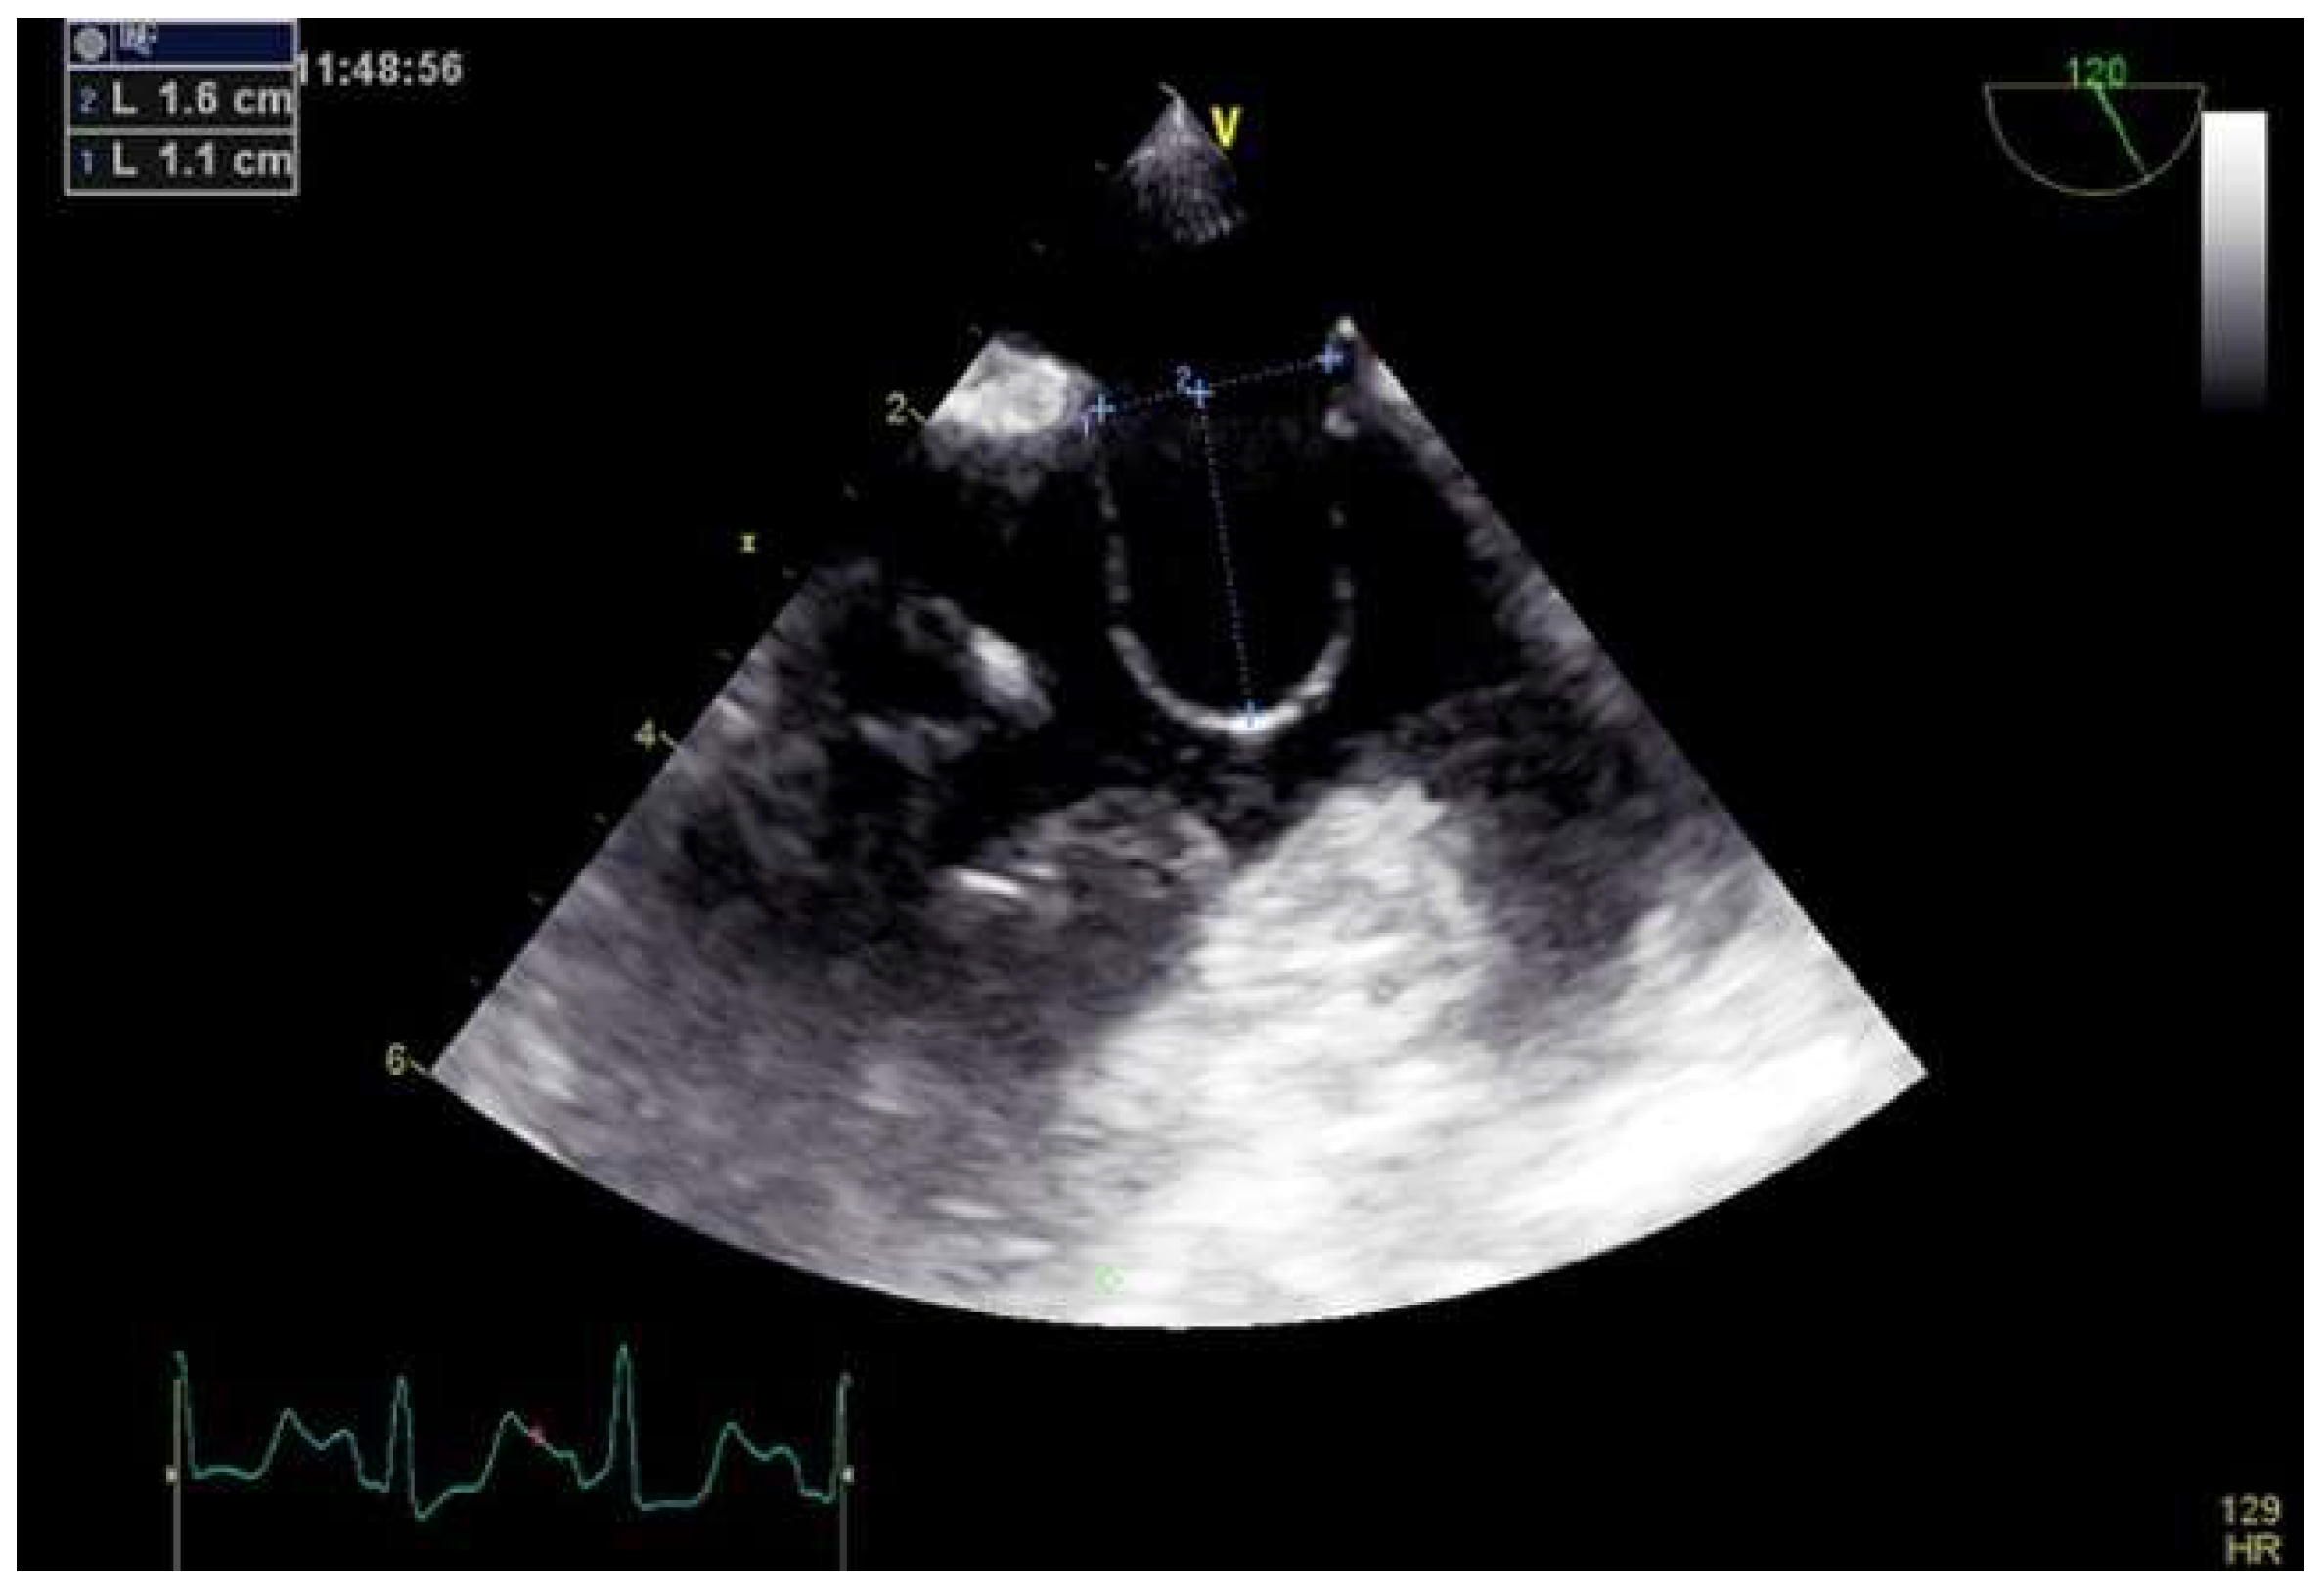

2.3.1. TEE before PFO Closure: Characterization of the PFO and Decision Making

3.4. Hypertrophy of the Septum Secundum